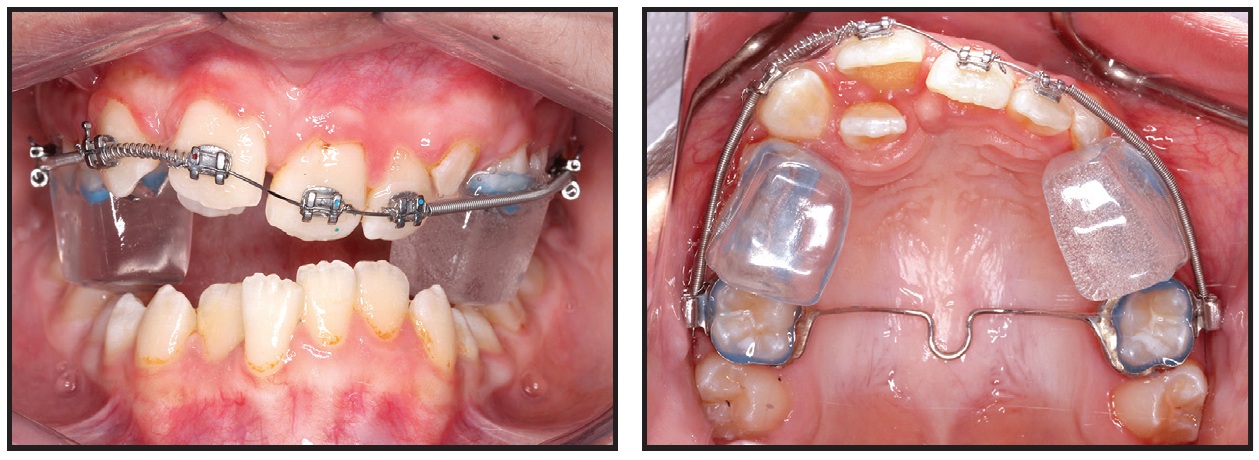

Fig. 2 Progress records. Posterior bite block in place.

The treatment plan and mechanics must be carefully designed to achieve the soft-tissue, skeletal, and dental treatment objectives. Here, the vertical dimension was managed with fixed posterior bite blocks, followed by a fixed anterior bite ramp and sequential segmented fixed appliances (Fig. 2). This approach required good patient compliance, but it successfully addressed the deep overbite, leveled the curve of Spee, increased the lower face height, and allowed for clockwise mandibular rotation.